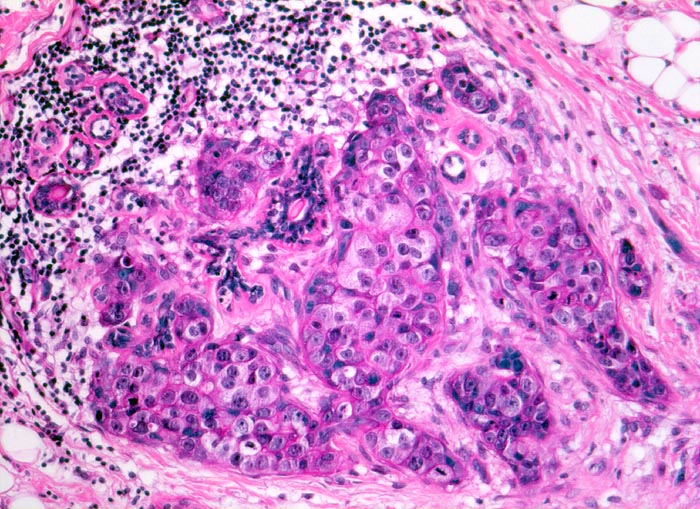

• Peritumorale Arterie mit assoziiertem dilatiertem Lymphgefäss mit intraluminalem Tumor (Lymphangiosis carcinomatosa).

•  Die Karzinominfiltrate bestehen aus schmalen soliden Zellsträngen, die keine Drüsenlumina ausbilden. Eine Myoepithelschicht fehlt. Kein assoziierter Mikrokalk.

• Mässig zahlreiche Mitosefiguren und Apoptosen.